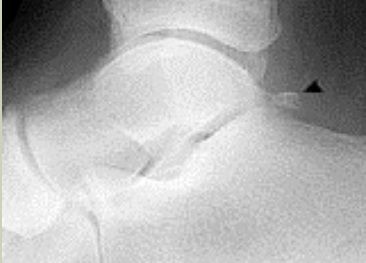

| What disease is this? What does the arrow indicate? | Rheumatoid arthritis. Arrow = Bone erosion secondary to inflammation of retrocalcaneal bursa. |